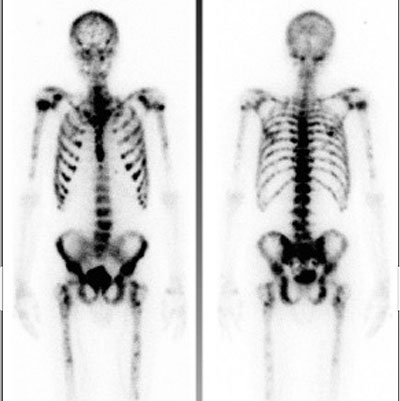

Spridd prostatacancer. Den amerikanske urologen Charles B Huggins fick Nobelpriset 1966 för att i början av 1940-talet ha infört kastrationsbehandling för män med spridd prostatacancer. De flesta män med spridd prostatacancer får en tids remission med kast­rationsbehandling, en del under många år, men fram till 2004 fanns det ingen effektiv behandling att ta till då kastrationsbehandlingen sviktade. Det var alltså ett stort framsteg när cellhämmaren docetaxel år 2004 visades kunna förlänga livet hos män med »kast­rationsresistent« metastaserad prostatacancer. Några år senare kom nya, kraftigare, hormonellt verkande läkemedel och radionuklidbehandling som kan förlänga livet ännu mer. Nu har vi även målstyrd behandling och effektivare radionuklider. Forskningen har visat att det lönar sig att redan från början kombinera flera systemiska behandlingar och att behandla primärtumören hos män med ett fåtal metastaser. Modern onkologisk behandling av prostatacancer beskrivs i artikeln av Thellenberg Karlsson et al.